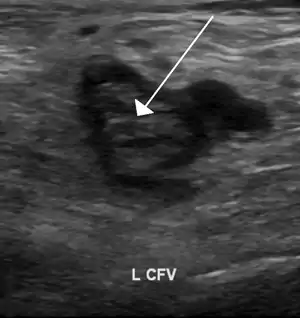

Compression ultrasonography for suspected deep vein thrombosis is the standard diagnostic method, and it is highly sensitive for detecting an initial DVT.[119] A compression ultrasound is considered positive when the vein walls of normally compressible veins do not collapse under gentle pressure.[39] Clot visualization is sometimes possible, but is not required.[120] Three compression ultrasound scanning techniques can be used, with two of the three methods requiring a second ultrasound some days later to rule out the diagnosis.[119] Whole-leg ultrasound is the option that does not require a repeat ultrasound,[119] but proximal compression ultrasound is frequently used because distal DVT is only rarely clinically significant.[118] Ultrasound methods including duplex and color flow Doppler can be used to further characterize the clot[118] and Doppler ultrasound is especially helpful in the non-compressible iliac veins.[120]

An ultrasound with a blood clot visible in the left common femoral vein. (The common femoral vein is distal to the external iliac vein.)